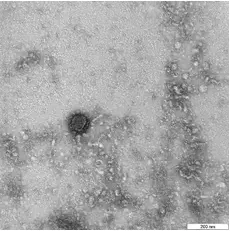

Ученые из Калифорнийского университета (США) обнаружили, что вирус SARS-CoV-2 имеет способность протягивать от пораженных клеток «зловещие щупальца», что позволяет инфекции быстро распространяться по организму. Об этом сообщает газета Financial Times со ссылкой на исследование, которое будет опубликовано в журнале Cell, передаёт LIVE Биробиджан.

По словам профессора Невана Кроган, возглавляющего проект, у клеток вируса существуют нити, которые протыкают оболочки других клеток.

Большинство вирусов, как отмечается, не вызывают роста подобных «щупалец». Это открытие помогло определить ряд медицинских препаратов, которые можно было бы использовать в борьбе против коронавируса, при этом большинство из них ранее разрабатывались для лечения рака, говорится в материале.